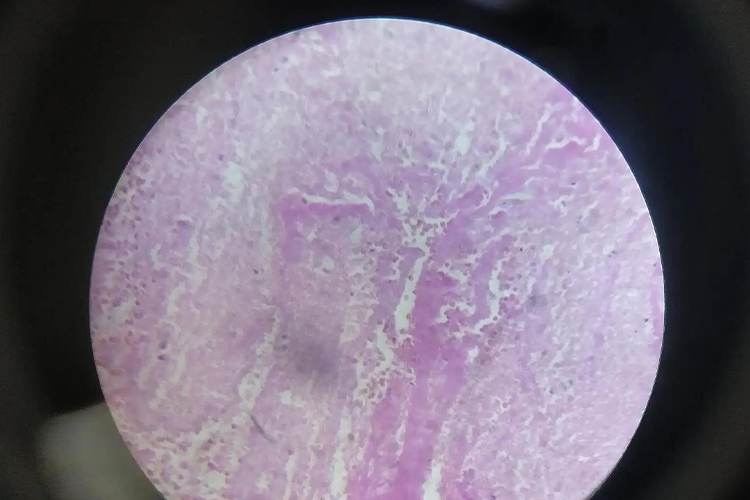

血管内混合血栓是血栓的一种分型,肉眼观呈灰白和红褐色的圆柱状,镜下由粉红色血小板小梁和小梁间纤维素网构成。

混合血栓多发于血流缓慢的静脉,肉眼观混合血栓呈粗糙、干燥的灰白和红褐色的圆柱状。镜下观混合血栓主要由粉红色分枝状或珊瑚状血小板小梁和小梁间充满大量红细胞的纤维素网构成,血小板小梁表面有许多中性粒细胞附着。